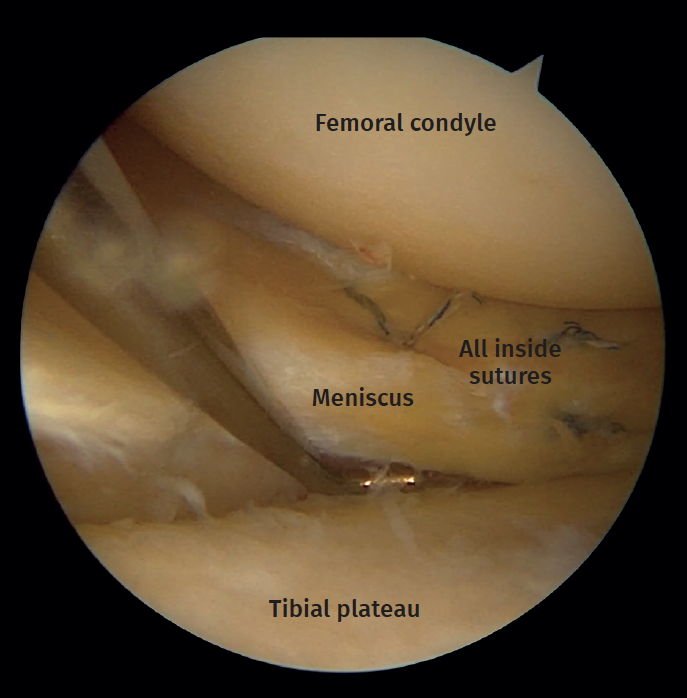

Of the 15 lateral meniscus injuries, there were 9 radial tears treated with partial meniscectomy and 6 peripheral tears that were sutured with a combination of an outside-in and an all-inside technique (Figures 7 and 8).

Figure 8. Right knee. View from the anteromedial portal. Probe placed in the anterolateral portal. Peripheral longitudinal meniscus tear sutured with an all-inside technique.